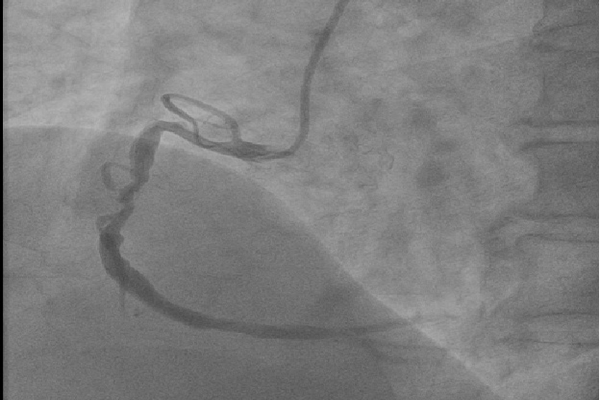

10月16日,入秋的夜晚已是寒冷刺骨,但在介入室內(nèi)我們心內(nèi)科的手術(shù)卻做的是熱火朝天。大家在徐曉輝主任的帶領(lǐng)下連續(xù)奮戰(zhàn)至凌晨2點半,雖然身感疲憊、汗流浹背,但是大家的內(nèi)心卻是無比激動的,因為我們?yōu)獒t(yī)院、為我們心內(nèi)科創(chuàng)造了一個“西北第一”,即“首例Resolute Integrity冠脈支架植入術(shù)”,為西北地區(qū)第一例在術(shù)中應(yīng)用該支架的病例。

運用最新的正弦波技術(shù)制作而成的Resolute Integrity冠脈支架擁有更好的通過性及順應(yīng)性,不僅確保了支架能夠順利通過更加迂曲、成角的病變,而且更加確保了支架植入在大于直徑4.0mm的冠脈內(nèi)能夠貼壁良好,從而保證了在冠脈恢復(fù)TIMI3級血流的基礎(chǔ)上減少術(shù)后急、慢性血栓的發(fā)生。

但是,光有支架還不行,還必須要有能夠駕馭它的人。而此次手術(shù)的患者,不僅僅是病變血管直徑較一般人粗,而且病變部位嚴重成角、迂曲,支架植入手術(shù)是非常困難的。擁有工匠精神的徐曉輝主任不畏困難、勇于挑戰(zhàn),在近20年介入手術(shù)經(jīng)驗的基礎(chǔ)上,運用嫻熟的操作技巧,厚積薄發(fā),成功地完成了我院首例5.0mm直徑冠脈支架植入手術(shù),術(shù)后效果堪稱完美!